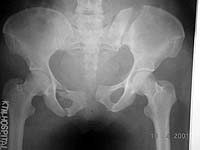

A female patient aged 40 years sustained pelvis fracture at different levels about a week ago. Kindly give your valuable opinions how to treat this difficult fracture? Image is attached herewith

This 40 year old woman in Turkey is a week after a pelvic ring disruption. Her injuries include a fracture of the left ilium posteriorly with displacement, a pubic symphysis disruption with about 5 cm of displacement and right superior pubic ramus and ischial ramus fractures. The left ilium fracture extends from the pelvic brim to the iliac crest and appears to begin anteriorly near the sacro-iliac joint.